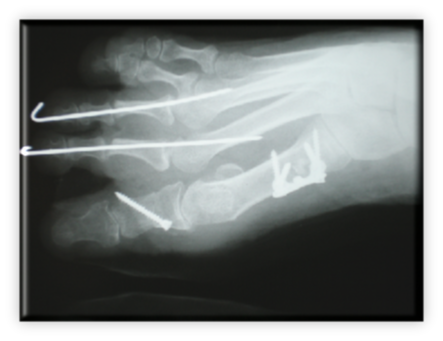

Πρόκειται για σύνθετη παθολογία του μεγάλου δακτύλου του ποδιού, που εκτός από την παραμόρφωση σε βλαισσότητα, όπως το όνομα υποδηλώνει, συνυπάρχει στροφική παραμόρφωση και γενικότερα παραμόρφωση ολόκληρου του πρώτου στοίχου (ταρσός, μετατάρσιο, δάκτυλο) αλλά και των μικρότερων δακτύλων. Πιο συγκεκριμένα, υπάρχουν οστεόφυτα στις αρθρώσεις και κυρίως στην έσω επιφάνεια της κεφαλής του πρώτου μεταταρσίου (κότσι), τροφικές αλλοιώσεις του δέρματος και δερματικοί κάλοι στα σημεία αυξημένης φόρτισης, λέπτυνση του υποδορίου λίπους στην πελματιαία επιφάνεια, εξάρθρημα σησαμοειδών οσταρίων, ανισορροπία στους άξονες έλξης των τενόντων περί του μεγάλου δακτύλου, υμενίτιδα στην έσω επιφάνεια της μεταταρσιοφαλλαγγικής η οποία είναι και πολύ επίπονη. Εμβιομηχανικά ο άξονας φόρτισης του ποδιού μεταφέρεται στο διάστημα μεταξύ πρώτου και δεύτερου στοίχου με αποτέλεσμα το πρώτο μετατάρσιο να δέχεται λιγότερα φορτία από όσο θα έπρεπε και τελικώς μεταταρσιαλγία στις κεφαλές των μικρότερων μεταταρσίων, παραμορφώσεις των μικρότερων δακτύλων με συχνότερη αυτή του δευτέρου που καταλήγει σε γαμψοδακτυλία, εφίππευση επί του πρώτου, στεόφυτα και δερματικό κάλο στην ραχιαία επιφάνεια της πρώτης φαλαγγοφαλαγγικής άρθρωσης, οστεοχόνδρινες αλλοιώσεις των αρθρώσεων και τελικά αρθρίτιδα.

ΒΛΑΙΣΟΣ ΜΕΓΑΛΟΣ ΔΑΚΤΥΛΟΣ (HALLUX VALGUS)

Στις ακτινογραφίες πρέπει να μετρηθούν η γωνία μεταξύ 1ου και 2ου μεταταρσίων με ανώτερα όρια 8-9 μοίρες, η γωνία βλαισσότητας του 1ου μεταταρσίου και 1ης φάλαγγας που όταν ξεπερνά τις 15 μοίρες ορίζεται παθολογική. Συμπληρωματικά μπορούν να μετρηθούν οι γωνίες προσανατολισμού της αρθρικής επιφάνειας κεφαλής 1ου μεταταρσίου και η γωνία προσανατολισμού κεντρικής αρθρικής επιφάνειας 1ης φάλαγγας του μεγάλου δακτύλου.

Αρχικά, η αντιμετώπιση είναι συντηρητική με αντιφλεγμονώδη επιθέματα, περιποίηση δέρματος, κινησιοθεραπεία αρθρώσεων, χρήση κατάλληλων υποδημέτων και ειδικών ναρθήκων ανάταξης.

Ο κατάλληλος χρόνος χειρουργικής αντιμετώπισης είναι εξειδικευμένος για κάθε περιστατικό, λαμβάνοντας υπόψη την ύπαρξη όλων των ανωτέρω παραμέτρων και την επίδραση που έχουν στη λειτουργικότητα αλλά και αισθητική του άκρου ποδός. Γενικότερα η επέμβαση δεν είναι απαραίτητο να γίνεται υπερβολικά νωρίς απλά και μόνο επειδή κάποιες γωνίες στις ακτινογραφίες είναι πάνω από το φυσιολογικό, αλλά ούτε και υπερβολικά καθυστερημένα  καθιστώντας το χειρουργείο πραγματική πρόκληση από τεχνική άποψη. Περιγράφονται περί τα 150 είδη επεμβάσεων για τη συγκεκριμένη παθολογία και τις παραλλαγές της. Είναι έργο του χειρουργού σε πλήρη συνεργασία με τον ασθενή να επιλεγεί η κατάλληλη επέμβαση για τον κατάλληλο ασθενή στον κατάλληλο χρόνο. Περιγράφονται επεμβάσεις από τις πιο απλές, συνθετότερες με τεχνικές ελάχιστης επεμβατικότητας έως και πολύ σύνθετες.